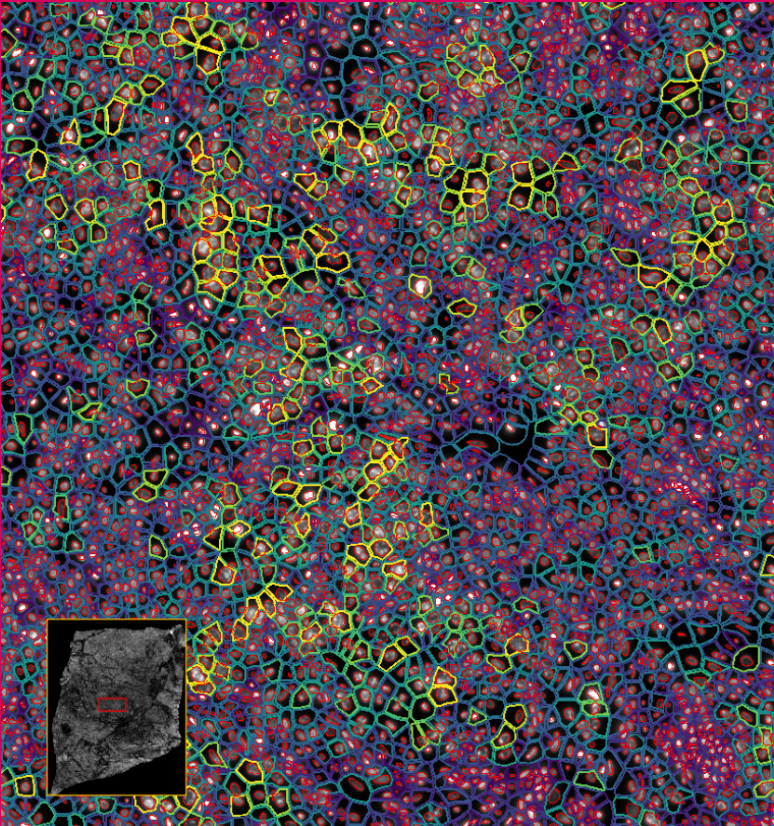

ͼ4-1£ºÊ¹ÓÃDAPI¶Ôϸ°ûºËȾɫ£¬ÍŽáÉî¶ÈѧϰҪÁìÍÆ¶ÏÍêÕûµÄϸ°û½çÏß

ͼ4-2£ºÊ¹ÓÃDAPI¶Ôϸ°ûºËȾɫ£¬ÍŽáÉî¶ÈѧϰҪÁìÍÆ¶ÏÍêÕûµÄϸ°û½çÏß